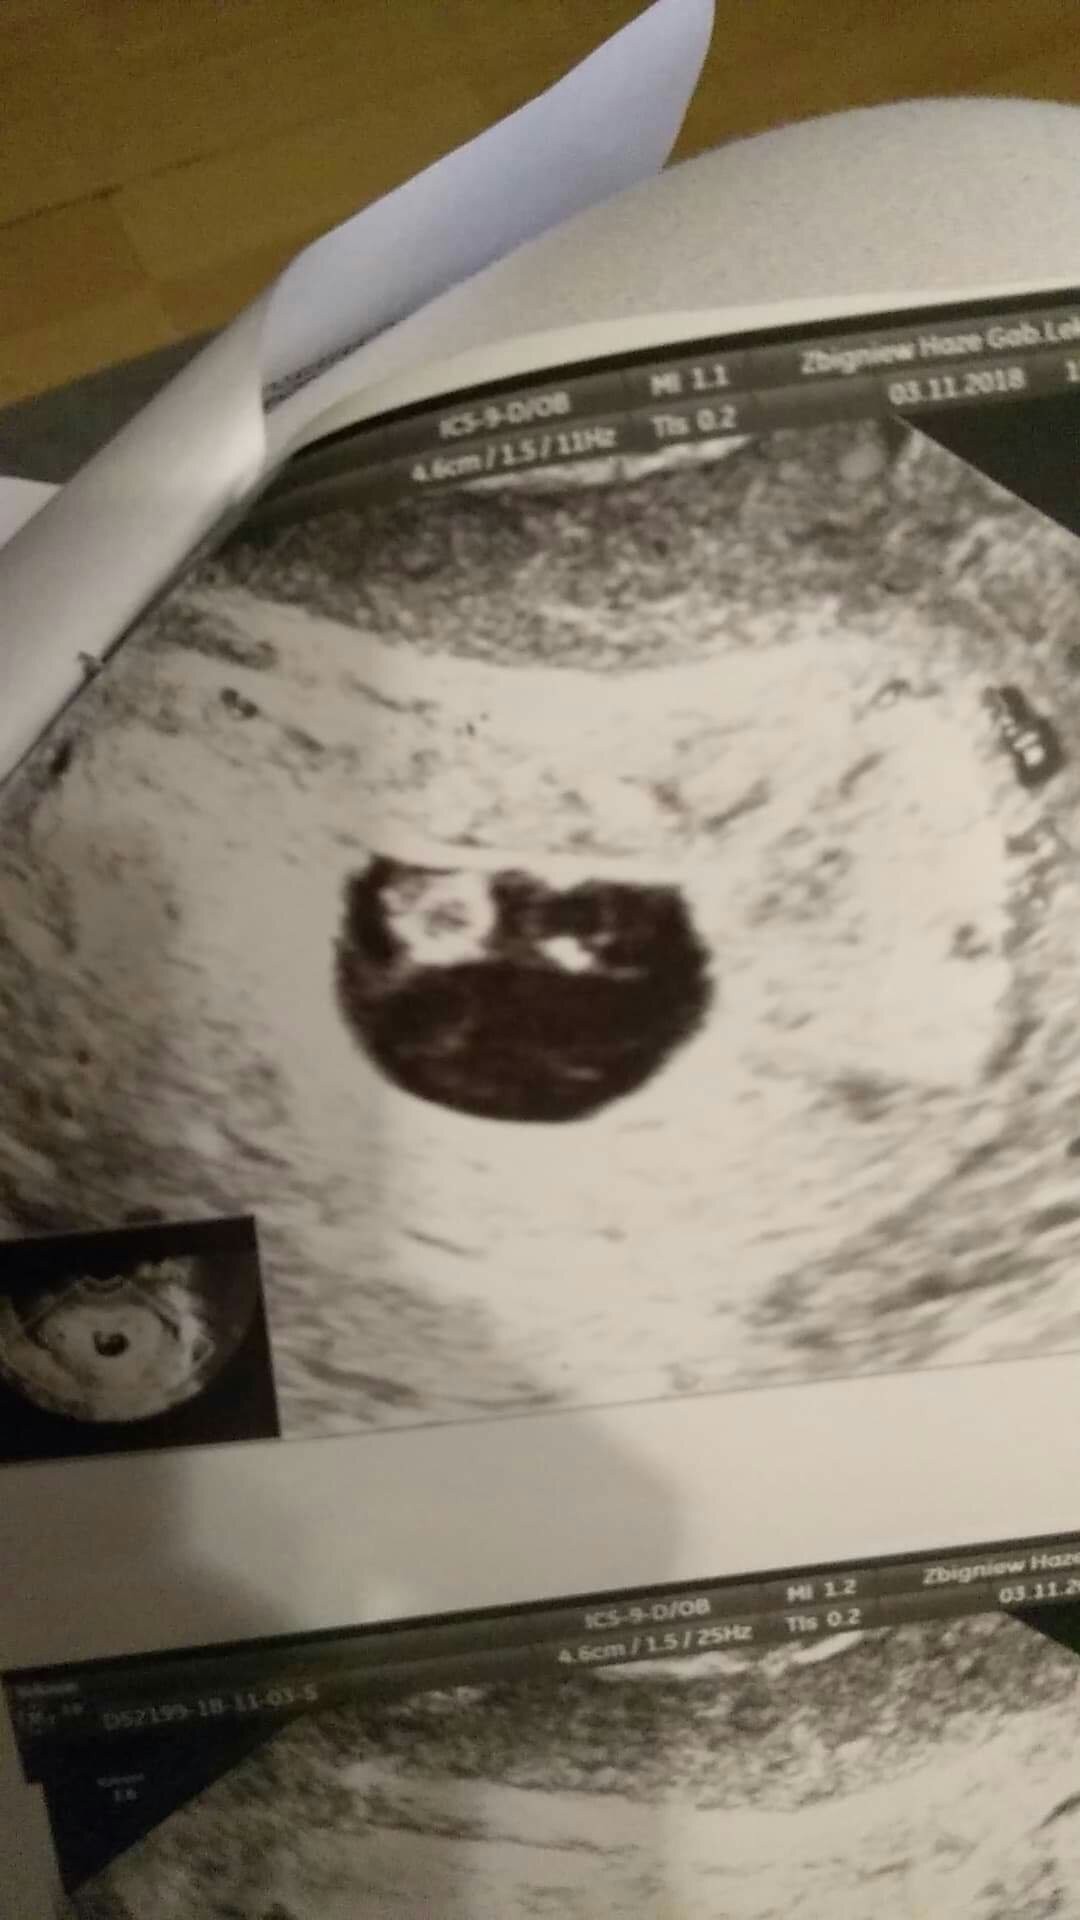

Powinnaś potwierdzić to u innego doktoraLekarz stwierdził że według niego ciąża się zatrzymała , że nie widzi oznak życia . My z mężem jeszcze nie wierzymy w to i wogole na zdjęciu widzimy dwa bąbelki

To kółeczko po prawej stronie to najpewniej pęcherzyk żóltkowy, ktory odżywia ciążę..Zobaczcie zdjęcie bo może to my wariujemy Zobacz załącznik 913370

Zastanawia nas tylko że wcześniej tego nie byloTo kółeczko po prawej stronie to najpewniej pęcherzyk żóltkowy, ktory odżywia ciążę..

A na zdjęciu wydaje mi się, że to może być pecherzyk zoltkowy(czy jakoś tak) który na początku ciąży odżywia zarodek, ale mogę się mylić.